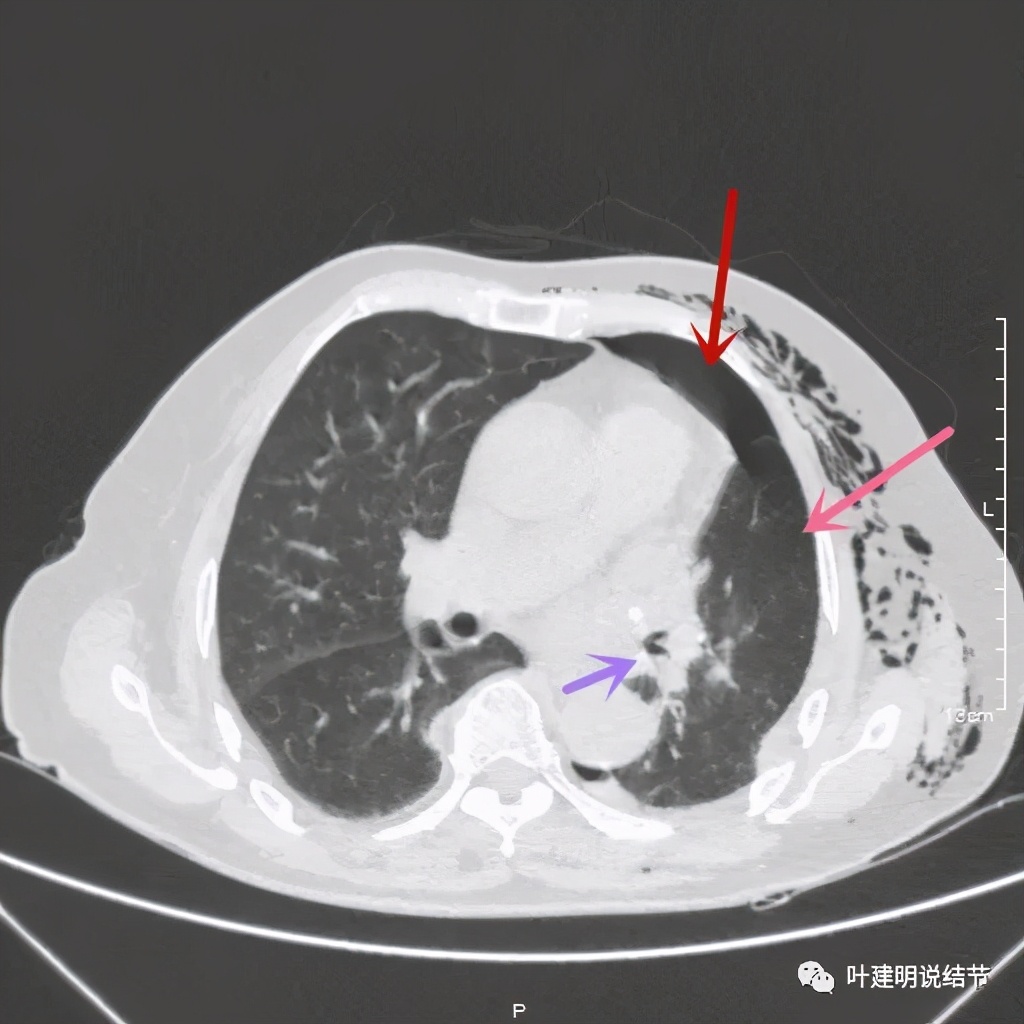

术后第二天患者乏力纳差,起不了床!而且CRP也大于100,我们的神经又紧张起来,怕支气管胸膜瘘,怕感染、怕有并发症发生。还好化验后是低钾,予以补充钾与镁2天后胃纳与精神均有明显改善,我们再加用静脉高营养支持治疗,补充白蛋白,情况逐渐好转。我们也于术后第4天查了CT,发现如下:

下叶膨胀良好

下叶膨胀良好,上叶残腔不大

下叶膨胀良好,上叶残腔不大,蓝色箭头示左主支气管

下叶膨胀良好,上叶残腔不大。桔色箭头示吻合口处,通畅

以上图像示下叶膨胀良好,上叶残腔不大,紫色箭头示吻合口以远的支气管通畅,肺膨胀佳